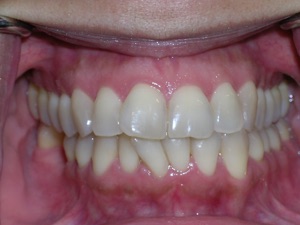

Here’s an example from a woman who had very significant crowding. There was a missing tooth on the bottom right. We considered extracting three other teeth, but decided not to.

Instead we decided to do braces and treat on a non extraction basis with trimming or shaving between teeth to create additional space.

We placed braces and begun a process of trimming or narrowing select teeth. Note that it is a painless procedure, and no anesthesia was needed.

Here are the results.